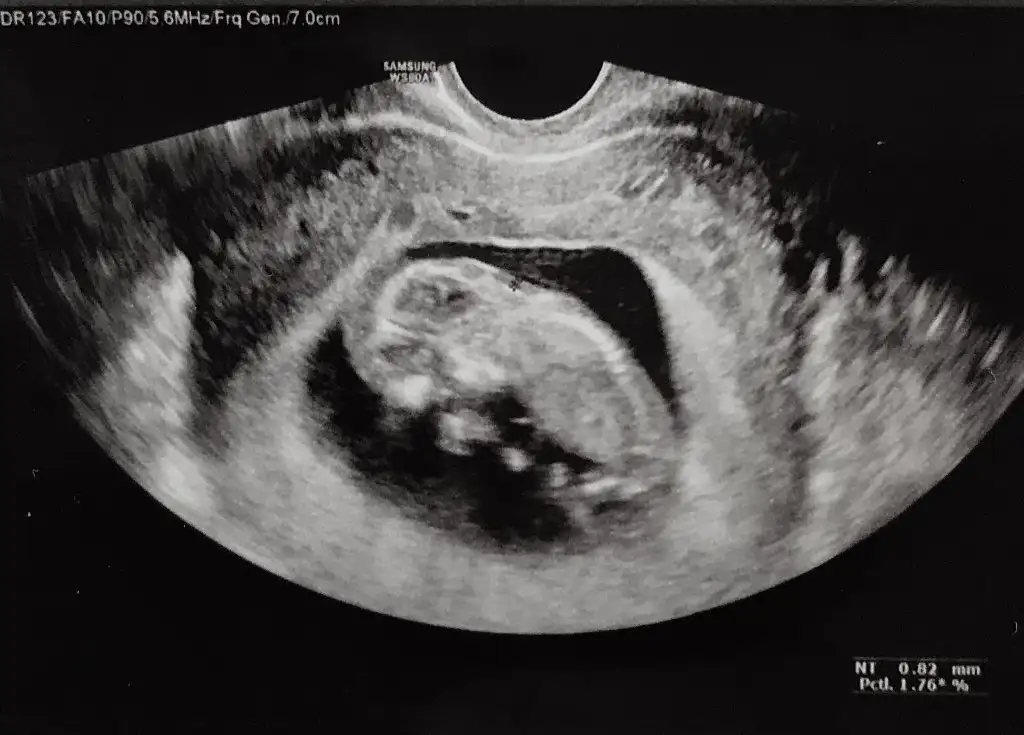

prenses gibi duruyor canımEki Görüntüle 3038369 8 haftalık bize de tahminde bulunurmusunuz karından bakıldı

bize de bakabilir misiniz 9 hafta ve 11 hafta vajinal ultrason görüntülerimiz